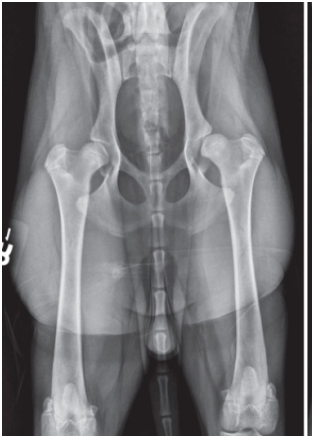

A seven-month-old Labrador Retriever is in your clinic for a routine screening of hip

dysplasia.

Name 3 abnormalities of the extended hip radiograph in the figure below?

• Subluxation of the left hip joint

• Poor femoral head coverage on the right hip joint

• Bilaterally femoral head metaphyseal sclerosis, but no signs of osteoarthritis